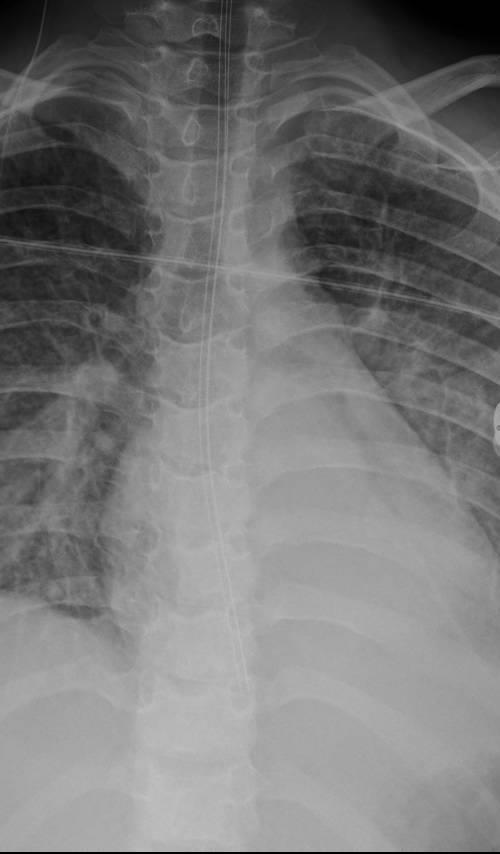

Imaging of Covid 19 infection in children CXR 8 38% 3% 51% 8%

Consolidation 35%

Collapse 3%

PeriBronchial thickening

51%

Hyperexpansion 7%

Effusion 4%

Imaging of Covid 19 infection in children CXR 9 C O V I D

Birmingham

Covid 19 CXR Imaging of Covid 19 infection in children